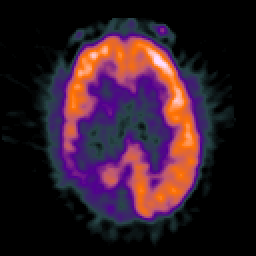

Glioma Overlay -- Slice #14

[Home][Help][Clinical] Slice 14